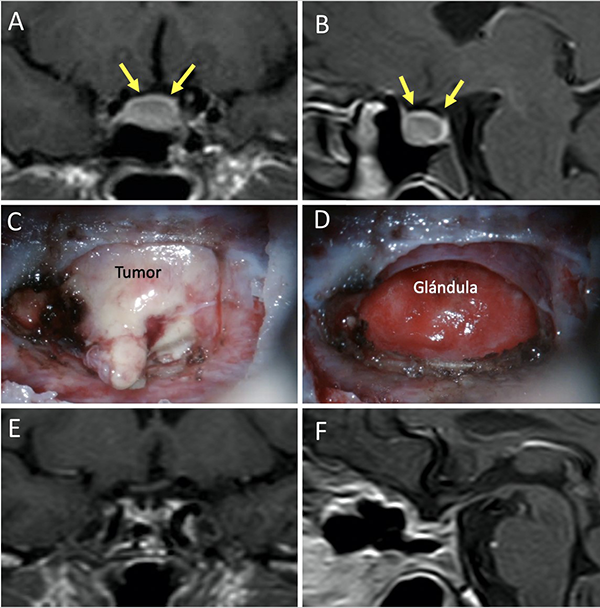

Una clasificación clásica de los adenomas es según su tamaño. Se los clasifica en microadenoma <10 mm (fig. 2), macroadenoma >10 mm (fig. 3), y adenoma gigante > 30 mm (fig. 4). Esta clasificación es importante ya que los índices de remisión están ligados al tamaño del adenoma y también su recidiva.12

Figura 2: Microadenoma. A-B: RM preoperatoria; C-D: RM postoperatoria.

Figura 6: Barrera selar fuerte. A-B) RM preoperatoria. C-D) Hallazgos intraquirúrgicos. E-F) RM postoperatoria. Flechas amarillas: interlinea > 1mm. Tomado de Campero A, Villalonga JF, Basso A. Anatomical risk factors for intraoperative cerebrospinal fluid leaks during transsphenoidal surgery for pituitary adenomas. World Neurosurg. 2019;124:346-55.